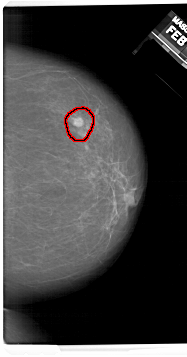

A_1409_1.LEFT_CC

RIGHT_CC LINES 6766 PIXELS_PER_LINE 3541 BITS_PER_PIXEL 12 RESOLUTION 43.5 OVERLAY

FILE: A_1409_1.RIGHT_CC.OVERLAY

TOTAL_ABNORMALITIES 1

ABNORMALITY 1

LESION_TYPE MASS SHAPE ROUND MARGINS ILL_DEFINED

ASSESSMENT 4

SUBTLETY 4

PATHOLOGY BENIGN

TOTAL_OUTLINES 1

BOUNDARY